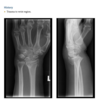

Anteroposterior view of the left wrist

(Fig. 2.13.1) shows an ulna that is shorter than the

radius (i.e., negative ulnar variance or ulnar minus

variance) and a lunate that is sclerotic and some-

what irregular in shape.

Kienböck disease (i.e., lunatomalacia)

Kienböck disease, or lunatomalacia, is

osteonecrosis of the lunate. It is most common in

­ patients 20 to 40 years old and has a predilection

for the dominant hand in individuals involved

in manual labor.

Cause unknown

shortened ulna

in relation to the radius (i.e., negative ulnar variance

or ulnar minus variance) is seen in up to 75% of pa-

tients with lunatomalacia and is considered a major

cause of the disorder

The imaging findings, which do not always corre-

late with the patient’s symptoms, include increased

density or sclerosis of the lunate and, eventually, alteration in the normal bony shape with collapse

on radiographs.

For example, in a 46-year-old

man with wrist pain, a coronal T1-weighted image

(Fig. 2.13.2) demonstrates low signal intensity in

the lunate (arrow) and negative ulnar variance. The

gradient-recalled echo MR image (Fig. 2.13.3) shows

the signal intensity within the lunate to remain low

(arrow). These features are diagnostic of osteone-

crosis (i.e., Kienböck disease). Surgical intervention

includes lunate replacement, radial shortening, and

ulnar lengthening.